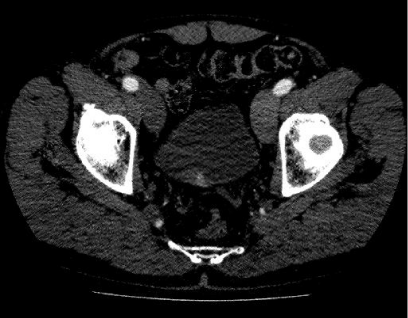

Follow-up flexible cystoscopy at 4months under local anaesthesia showed recurrence of the larger, incompletely resected 2cm bladder lesion (Figure 4). Subsequent CT scan with contrast showed a lesion on the right bladder wall. The abdominal organs showed no abnormality and there was no abdominal or pelvic lymphadenopathy (Figure 5). A Pelvic MRI showed an enhancing area of thickening on the right bladder wall with ill-defined peri-vesical fat in that area (Figure 6). The patient had a further cystoscopy and complete resection of the bladder lesion was achieved due to less inclusive calcification. Histology confirmed amyloid deposition, with apple-green birefringence, with extensive ossification and accompanying giant cell reaction and no evidence of malignancy. Immunochemical staining of amyloid deposits, using monospecific antibodies reactive with serum amyloid a protein (SAA), transthyretin (TTR) and Kappa and Lambda immunoglobulin chains was negative. Therefore, the conclusion was that the amyloid is of non-AA type. A further follow up with flexible cystoscopy under local anaesthesia every 6months showed no recurrence of the amyloid lesion in the bladder up to two years after the second resection (Figure 7).

Figure 5 Non-invasive bladder lesion on the right bladder wall on a contrast CT scan.

Figure 6 Non-invasive bladder lesion on the right bladder wall on a contrast CT scan.